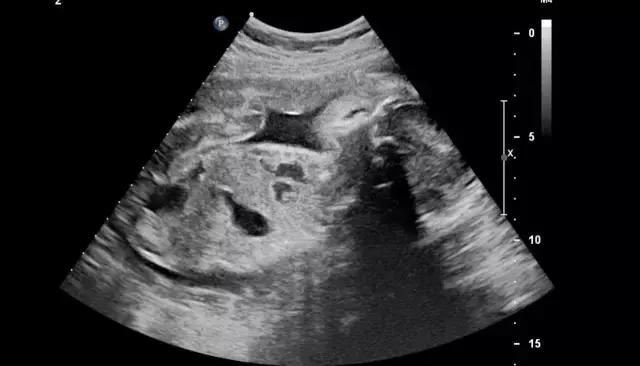

终于轮到我了。我绷紧神经,先到床头拿了一张纸放在床中央,坐上去准备脱右腿裤子时,突然发现自己穿了靴子,两只都脱,会耗时过长,大脑飞速转过医生等得不耐烦的样子,顿时慌乱了。“两只鞋子都要脱吗?”我问医生,问完我就后悔了。等待她的回答很漫长,长到我有足够时间把它们都脱下来。医生最终也没理我,撕开一个好像安全套似的袋子,取出套子,套在一根长长的检查器上,然后板着脸把它插进阴部。

我的心情非常复杂,不敢喊疼又有些恐惧。“多大了?”医生面无表情问我。“我吗?”我不清楚她问的是我,还是腹中的胎儿。

“几个月了?”她补充了一句。

“我不知道,医生没说,我自己查是5周。”

“还看不到。”她拔出检查器,打出检查单,“下一个。”

我的心凉了半截,慌乱穿好裤子,接过检查单,再次上楼进了医生办公室,里面已经有七八个人,我学着其他孕妇的样子,把B超单放在白口罩医生桌上,她扫了一眼,小声含糊说:“孕期太小了还看不到,下周再过来复查一次。”然后在打印机上又刷出了四五张单子,递给我:“验血,下周拿报告”。